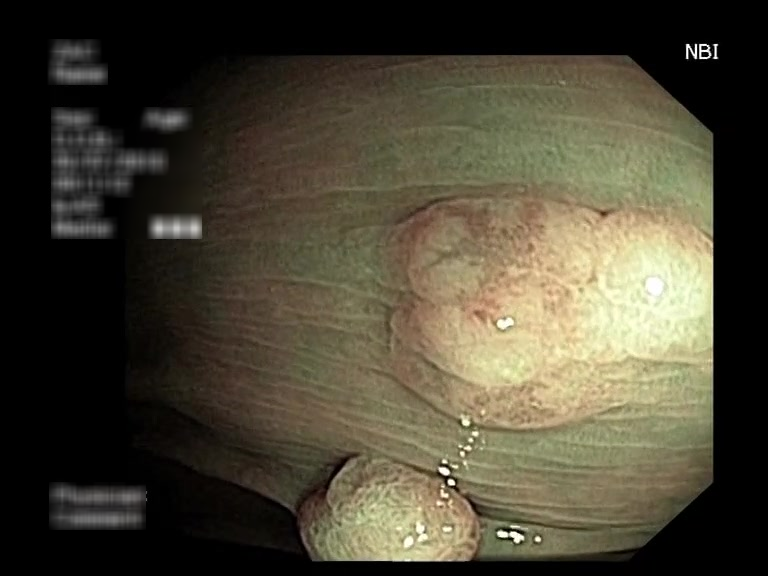

| Lesion | White Light Frame | NBI Frame | White Light Video | NBI Video | Camera Calibration |

| serrated_01 |  |

|

WL.mp4 | NBI.mp4 | cam.xml |